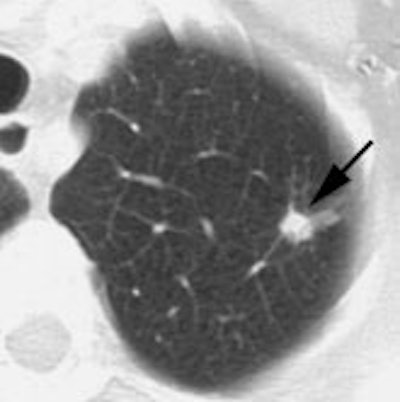

Example: The CT scan in this patient demonstrated a small nodule in the left upper lobe (black arrow). PET-FDG images demonstrate very intense accumulation of the tracer within the lesion (white arrow), which was a non-small cell lung cancer. (Case courtesy of H. Page McAdams MD, Department of Radiology, Duke University Medical Center) |